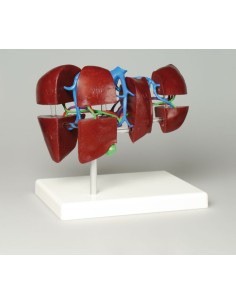

Découvrez le monde de l'anatomie avec des modèles anatomiques de précision

Bienvenue sur Tuttoanatomia.it, le portail de référence en Italie pour l'achat de modèles anatomiques, de posters, de lits portables, de simulateurs médicaux et de littérature spécialisée. Grâce à nos modèles anatomiques de pointe de 3B Scientific et Erler Zimmer, nous offrons une expérience d'apprentissage inégalée.

Des modèles anatomiques détaillés pour tous les besoins

Du crâne en 22 parties à verrouillage magnétique aux modèles de colonne vertébrale, des modèles d'articulation aux modèles de cœur, chaque pièce de notre collection est conçue pour une immersion totale dans l'étude de l'anatomie humaine. Nos modèles, réalisés à partir de scans d'os réels, garantissent une expérience tactile authentique et une fidélité de poids presque identique aux originaux.

Indispensables aux étudiants comme aux professionnels, nos modèles anatomiques sont des outils pédagogiques qui permettent d'observer les structures anatomiques avec précision, en évitant les dissections ou les études invasives. Ils sont également utiles pour expliquer les pathologies aux patients, ce qui rend la communication plus efficace et permet de gagner un temps précieux.